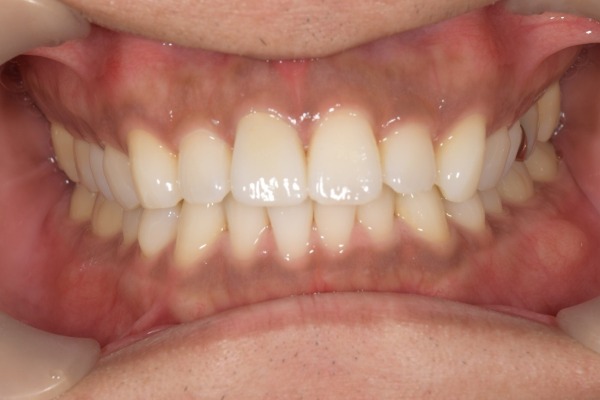

こちらが仮歯の状態です。